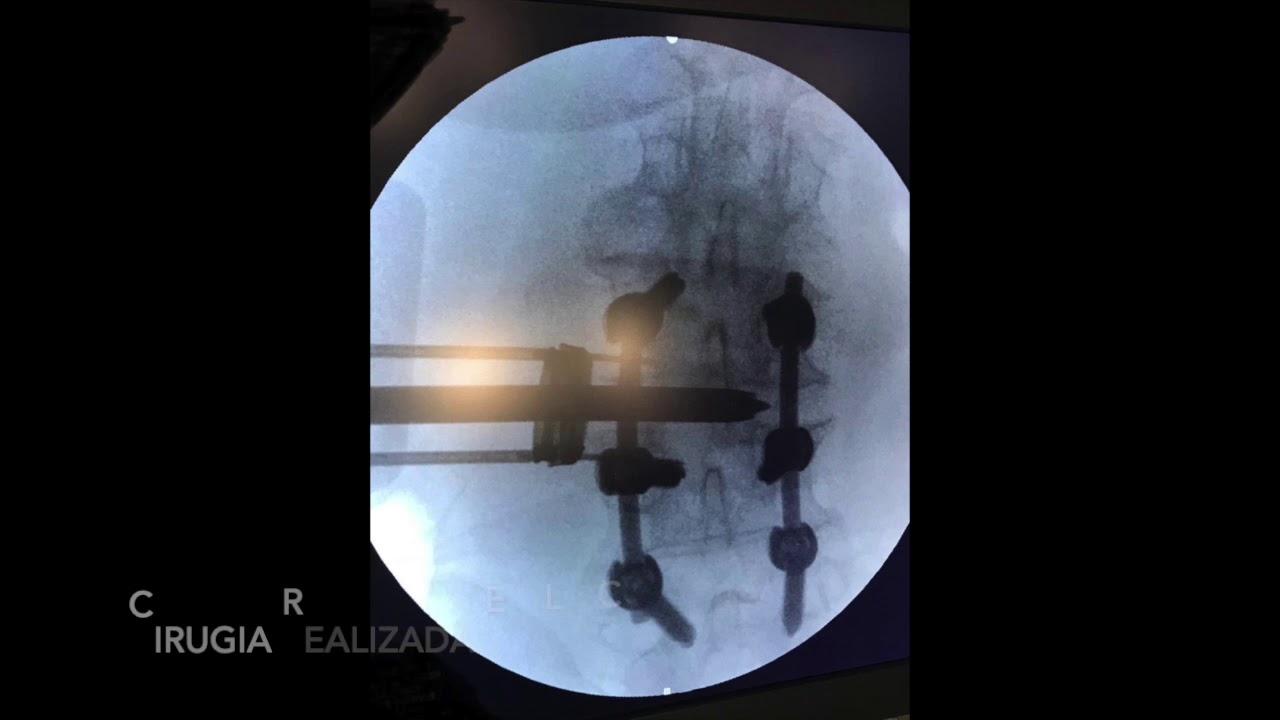

Cirugía espinal mínimamente invasiva

La cirugía percutanea minimamente invasiva en columna esta demostrado que es un procedimiento efectivo y seguro. Reduce el dolor postquirúrgico, reduce la posibilidad de transfusión por la poca perdida de sangre, minimiza el riesgo de infección al ser una cirugía cerrada y sobre todo la recuperación del paciente es mucho mas rápida, logrando ponerse de pie y empezar a andar enseguida y tambien disminuye el ingreso hospitalario. Ademas al no lesionar la musculatura disminuye la posibilidad de inestabilidad del segmento superior o inferior tras la cirugía.